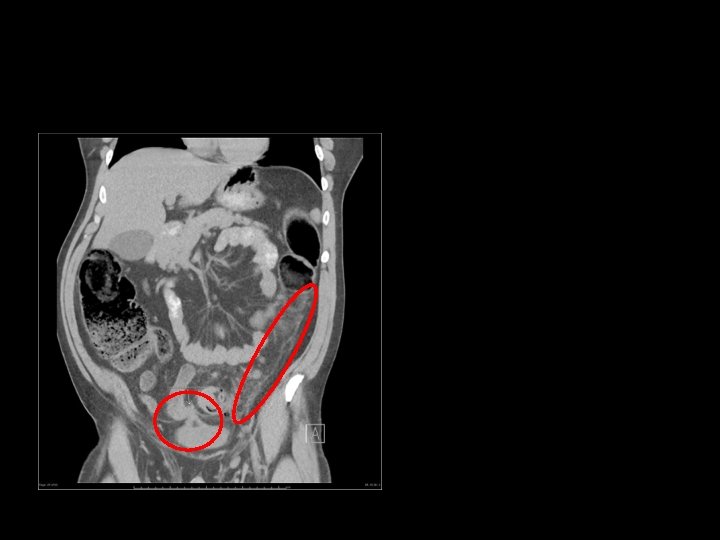

Large bowel obstruction (LBO) are often impressive on imaging, on account of the ability of the large bowel to massively distend. This condition requires prompt diagnosis and treatment. Large bowel obstructions are far less common than small bowel obstructions, accounting for only 20% of all bowel obstructions. Large bowel obstructions is age-dependant the most common cause is colonic cancer (50 -60%), typically in the sigmoid The second most common cause in adults is acute diverticulitis (involving the sigmoid colon). Together, obstructing tumours and acute diverticulitis account for 90% of all causes of large bowel obstruction.